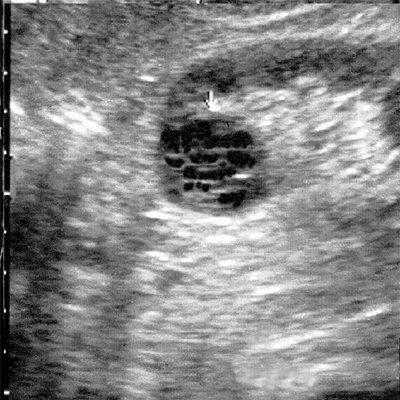

Результаты исследования: размеры плода пропорциональные, соответствуют менструальному сроку беременности. При эхокардиографии особенностей строения сердца у плода не выявлено. При оценке органов мочевыделительной системы обнаружено следующее: правая почка плода нормальных размеров и структуры. Левая почка увеличена до размеров 53х38х46 мм при 95-м процентиле нормативных для срока значений 43х24х23 мм [4] (рис. 1). В структуре почки, преимущественно в верхнем и среднем сегментах, определяется округлое образование без четких контуров, средней эхогенности, приблизительные размеры его 50х35х35 мм. При цветовом допплеровском картировании в образовании визуализируется обширная сосудистая сеть. При допплерометрии индексы сосудистой резистентности (рис. 2) в разных участках образования варьируют в широких пределах (от 0,49 до 0,77).

Рис. 1. Почки плода в режиме 2D. Видна разница в эхографической структуре. Границы почек обозначены стрелками.

Мезобластическая нефрома - это односторонняя округлая солидная опухоль без капсулы, однородной структуры, иногда содержащая кистозные включения, образующиеся за счет кровоизлияний или очагов некроза. Микроскопически опухоль представлена мезенхимальными клетками, к которым относятся гладкие мышечные волокна и незрелые фибробласты. Кроме того, она может содержать клеточные элементы почечных клубочков и трубочек. Эта опухоль не имеет капсулы и способна к инфильтрирующему росту. Опухоль хорошо васкуляризирована и имеет развитую сосудистую сеть [4].

При ультразвуковом исследовании в пренатальном периоде опухоль определяется как округлое образование, как правило, больших размеров, без четких контуров. Разница в акустической плотности интактной почечной паренхимы и опухолевой ткани может создавать эффект границы, которая глазом будет восприниматься как капсула. В большинстве случаев при беременности, осложненной возникновением мезобластической нефромы, регистрируется многоводие. Сочетанные изменения в других органах и системах плода встречаются редко.